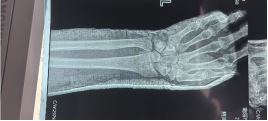

術前影像

患者男性,54歲,外傷致右側脛腓骨開放性骨折8小時,局部可見右側脛骨骨折近端露出···